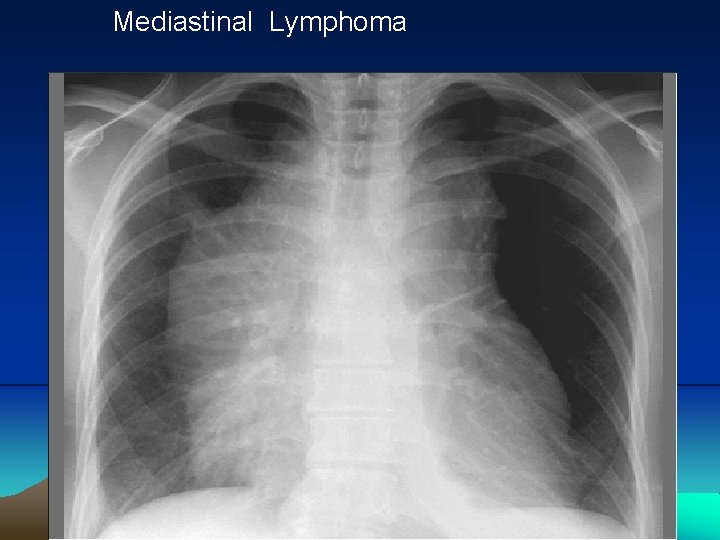

Mediastinal Lymphoma

Mediastinal Lymphoma